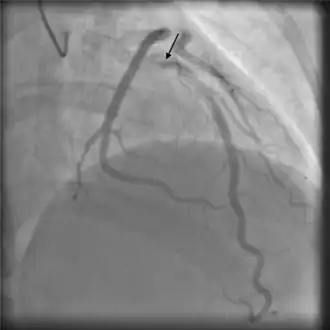

Angiography

Angiographic appearances of SCAD fall into three categories.[13] Type 1 lesions appear as classic angiographic dissections, with a false lumen distinct from the true lumen. These are the easiest to identify as SCAD clinically, though relatively uncommon.[13] Type 2 lesions - the most common subtype of SCAD - appear as a long, smooth narrowing of the vessel without a distinctly visible false and true lumen.[6] Type 3 lesions appear similar to atherosclerotic lesions and are difficult to confirm as SCAD through angiography alone,[16] possibly requiring the use of intracoronary imaging.

Angiographic image-contrast was seen to swirl and stay longer than usual, consistent with self-limiting spontaneous coronary artery dissection